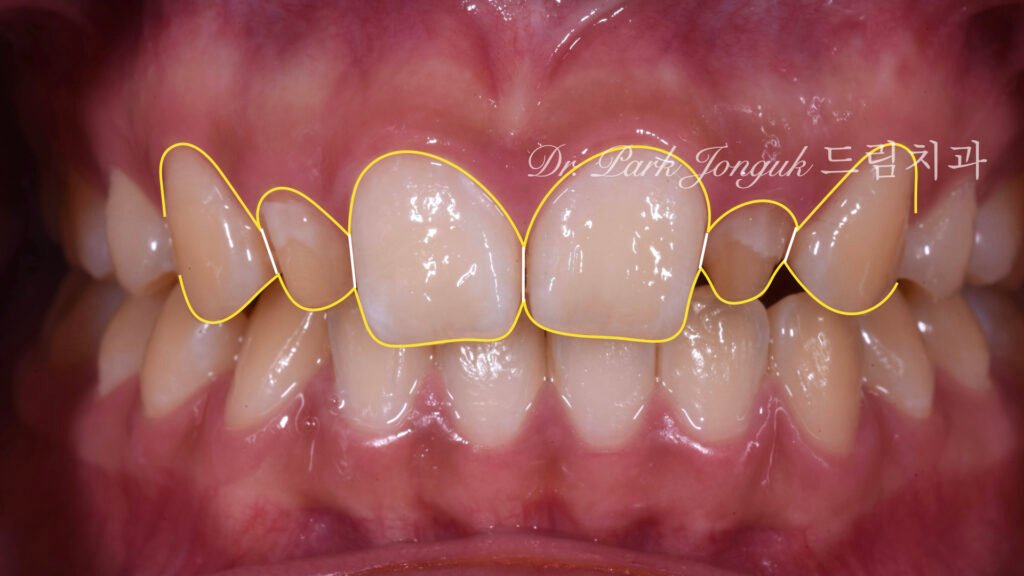

현재 치아 상태를 디지털 사진으로 촬영한 후, 그래픽 소프트웨어를 사용하여 목표 형태를 그림으로 표현했습니다. 이 시각화 작업은 환자와의 소통뿐 아니라, 임상의와 기공사 간의 명확한 의사소통 도구로 작용합니다.

중절치 크기 조정의 필요성 왜소측절치만 무삭제로 확대하고 비대한 중절치를 그대로 두면, 전체 비율이 더욱 악화됩니다. 따라서 중절치에 대한 적절한 치아 준비가 필수적이라는 결론에 도달했습니다. 이는 “왜소측절치는 항상 무삭제”라는 단순한 공식에서 벗어나, 전체 치열을 고려한 맞춤형 접근의 필요성을 보여줍니다.

비율 최적화 목표 중절치와 측절치의 비율을 생리학적으로 이상적인 범위로 조정합니다. 지나치게 큰 중절치를 적절히 축소하고, 왜소한 측절치를 정상 크기로 확대하여 균형 잡힌 미소를 만듭니다.

치아 간 비율: 왜소측절치는 정상 크기로 확대되었고, 비대했던 중절치는 적절한 크기로 축소되어 전체적으로 조화로운 비율이 만들어졌습니다. 중절치:측절치 비율이 생리학적 이상 범위에 도달하여, 더 이상 특정 치아가 유독 크거나 작아 보이지 않습니다.